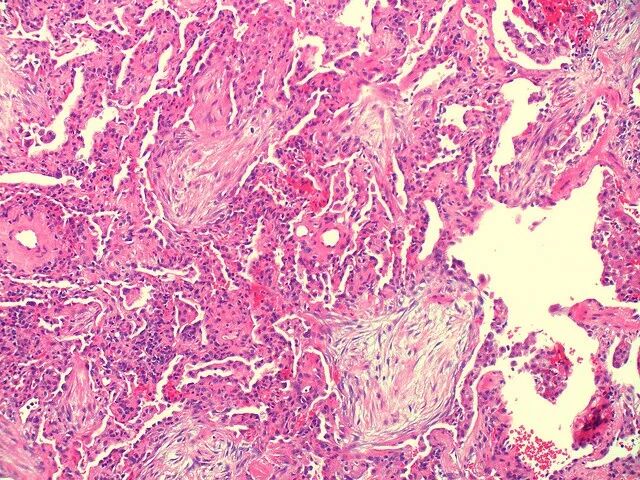

肺泡腔内肉芽组织呈芽生状,由疏松的结缔组织将成纤维细胞包埋而构成,可通过肺泡孔从一个肺泡扩展至邻近的肺泡,形成典型的“蝴蝶影”。

图片

注:典型的蝴蝶样肺泡内肉芽组织。